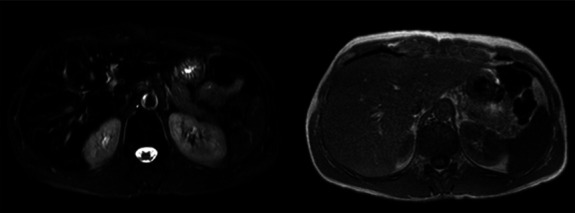

Abstract Image